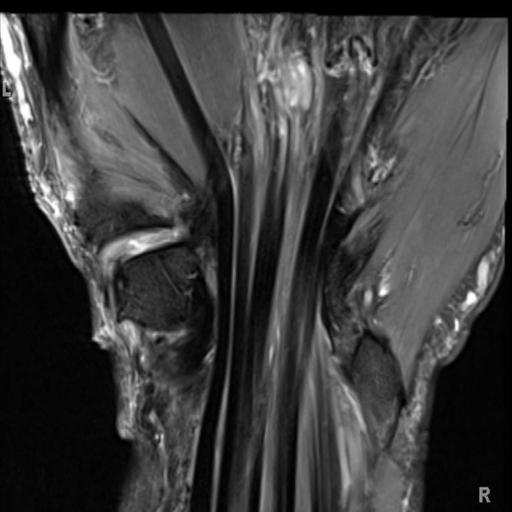

Carpal Tunnel X Ray Findings . Carpal tunnel syndrome (cts) is a collection of symptoms and signs caused by compression of the median nerve in the carpal tunnel at the wrist. Mri can detect abnormalities of the median nerve, flexor tendons, vascular structures, and transverse carpal ligament in the region of. Physical examination mainly useful for ruling out other diagnoses. Symptoms include numbness and/or tingling of the thumb and radial fingers, aching wrist, and clumsiness. Carpal tunnel compression test (durkan's test) is the most sensitive test to diagnose carpal tunnel syndrome. Cts is the most common compression neuropathy of the upper limb and is three times more common in women than men.

Cts is the most common compression neuropathy of the upper limb and is three times more common in women than men. Mri can detect abnormalities of the median nerve, flexor tendons, vascular structures, and transverse carpal ligament in the region of. Carpal tunnel compression test (durkan's test) is the most sensitive test to diagnose carpal tunnel syndrome. Carpal tunnel syndrome (cts) is a collection of symptoms and signs caused by compression of the median nerve in the carpal tunnel at the wrist. Symptoms include numbness and/or tingling of the thumb and radial fingers, aching wrist, and clumsiness. Physical examination mainly useful for ruling out other diagnoses.